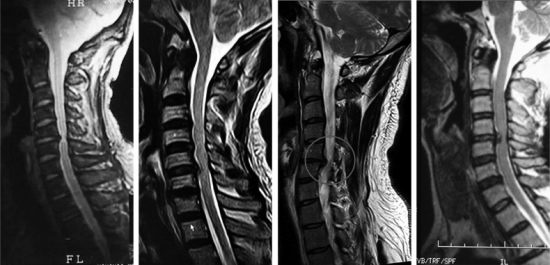

拍片检查,多在5-6-7下颈椎有病变。